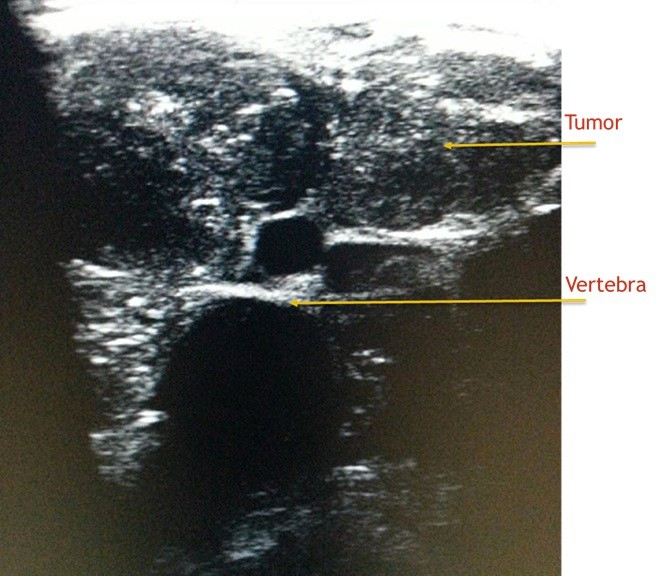

Till i spoke to him ,i thought he had a common easily curable illness.I learnt from him that ,in last 3 months he consulted 2 doctors,one of them a surgeon with no respite.One had treated him empirically and while  the other had referred him to a vascular surgeon,specialist dealing with blood vessels of legs .The vascular surgeon rightly requested a blood vessel study(Doppler ultrasound test)of the leg.I did a detailed examination of veins and arteries of the leg and found them normal.And  radiologists do not stop till they unearth the mystery of diagnosis.I gently interrogated his abdomen with ultrasound.I was not happy with what i found.It was a  dangerous tumour (sarcoma )involving muscles and deep structures of abdomen(retro peritoneum)impeding the fluid flow from leg and hence causing its swelling. Had the radiology scan been performed earlier,delay in diagnosis could have been avoided.

One cannot neglect leg swelling irrespective of the age.Appropriate diagnostic scanning should be carried out in consultation with radiologist.